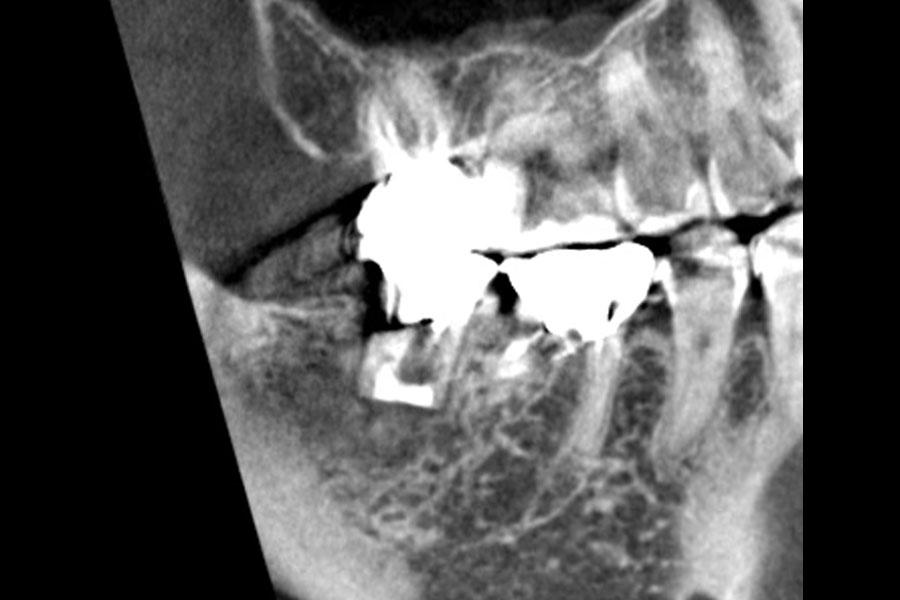

治療前